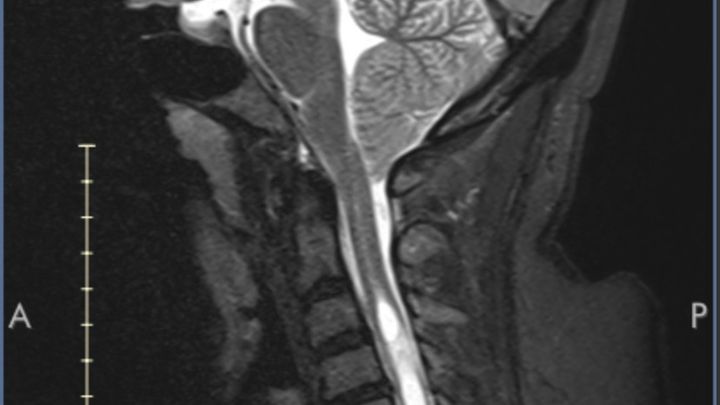

I’m Candice a 39 yr mom of two who started feeling sicker than my norm as someone who already has an auto immune disorder Im not new to feeling unwell. My bodily functions began to deteriorate slowly to the point where my grasp has faded in my hands, swallowing became difficult as well as holding my breath to even not be able to hold my urine. I went in for an MRI thinking it’s just sciatica in my neck. NOPE THAT WOULD'VE BEEN A BLESSING I GET THE RESULTS I HAVE WHATS CALLED A CHIARI MALFORMATION. Which most people who have the type that I have usually are born with from not developing properly as a fetus from a number of things in my case the drs believes it was from my mothers drug use. I now have to undergo a Chiari decompression surgery which is where the remove a section of the base of the skull and a piece of the spinal cord and this will require me to be out of work for at least 3 months. I’m not comfortable with putting this out here but it’s could use all the help I can get to make sure I don’t fall to behind on basic bills as well as extra bills now like laundry as I’m not allowed to lift anything or bend in half I also live on a 4th floor walk up so now I need someone to do this as well as buying my groceries and things like this. I have help but my family also can’t be here all the time. So I’m asking for any bit of help anyone can give even if it’s just a share. I want to say thank you ahead of time for anyone who helps out in anyway possible May you all be blessed.